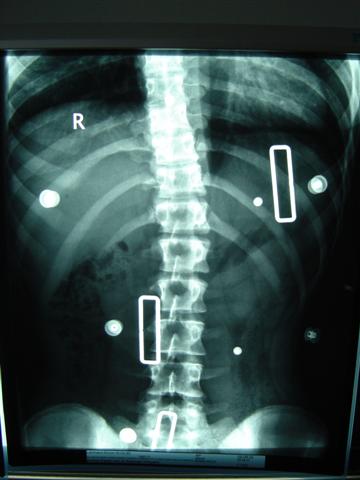

ich war heute in Dresden zum Röntgen gewesen. Musste erst zur Anmeldung, den Schein fürs Röntgen holen und dnan zum Röntgen gehen. Dort stand oben, das ich nur im Tgaeskorsett geröngt werden soll. Wir uns dann beschwert, weil aj nciht im Nachtkorsett geröngt wurde. Also ham se bei der Anmdelung vom dem Orthopädiehaus angerufen und ich konnte doch noch geröngt werden. Und als der Oberarzt die Röbis vermessen hat konnte er es fast selber nicht fassen!! Mein Tgaeskorsett korrigiert die lumbale Krümmung von 37° auf 12° !!!!! Ihr könnt euch gar nicht vorstellen, wie happy ich in dem Moment war, weil ich da die ganze Zeit an Fine und ihre Korsetts denken musste. Meine obere Krümmung wird im Tageskorsett nicht korrigiert, weil diese sehr weit oben sitzt und mein Arm einschläft, wenn er angehoben wird. Aber von den 34° ohne Korsett sind 28° es steht zwar 18° auf dem röbi, aber der Unterschied zu den 12° ist doch zu groß. Wir haben die Röbis auch fotografiert, ich stelle die Bilder dann demnächst hier rein. Im Nachtkorsett ist die untere Krümmung 13 °, und weil die irgendiwe im Liegen nicht die ganze WS röntgen können, kann die obere nicht vermessen werden

Noch mal die Werte im Überblick:

1. Röntgen, 1.3.05: 29° im BWS-Bereich, 32° in der LWS

2. Röntgen, 25.4.05: 34° in der BWS und 37° in der LWS (beides um 5 grad verschlechtert, die Ärzte hatten mir nicht mehr zu viel Hoffnungen gemacht)

3. Röntgen im Korsett, 29.8.05: 28° und 12°